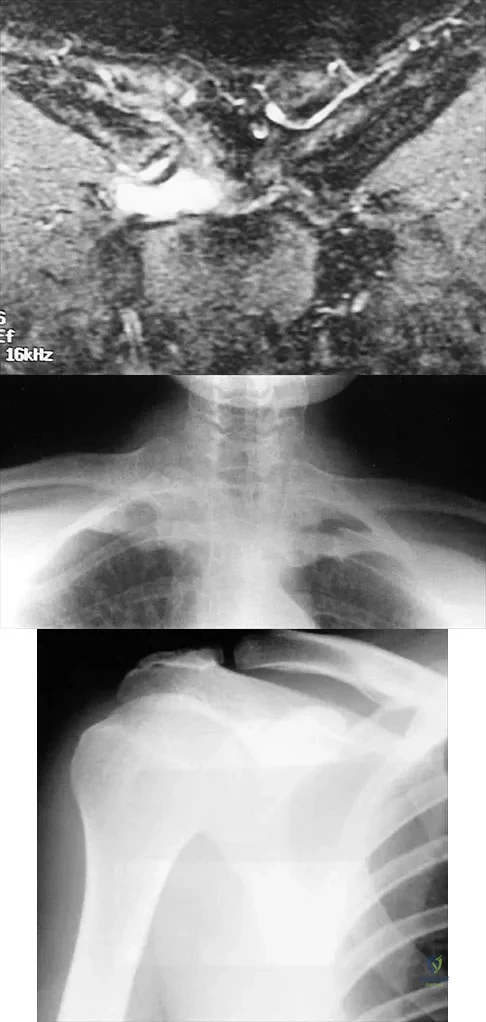

A 54-year man has left shoulder pain and weakness after falling while skiing 4 months ago. Examination reveals full range of motion passively, but he has a positive abdominal compression test and weakness with the lift-off test. External rotation strength with the arm at the side and strength with the arm abducted and internally rotated are normal. MRI scans are shown in Figures 1a and 1b. Treatment should consist of

Detailed Explanation